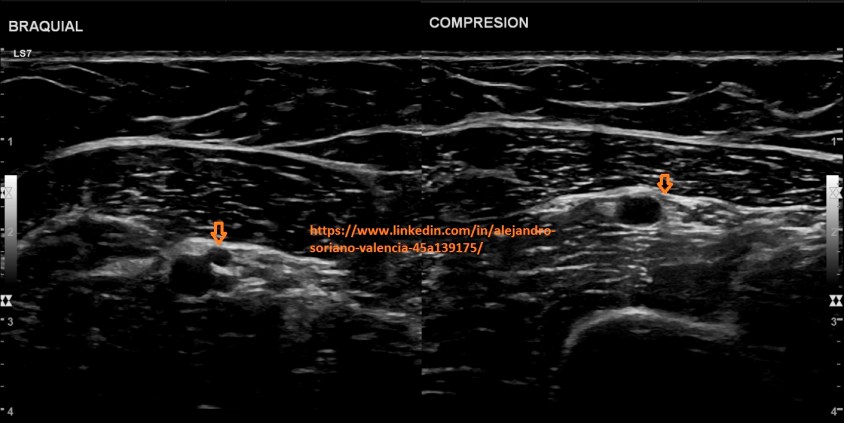

o Braquiales.

Brazo extendido en posición anterior. Nos servirá de guía la

arteria braquial para identificar las dos venas adyacentes a ella.

Arm extended in anterior position. The brachial artery will guide us to identify the two veins adjacent to it.

7. Braquiales transversal.

8. Braquial longitudinal. Estudio triplex.